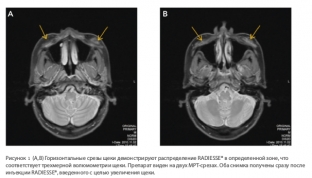

Thus, one of their studies was concerned with the guarantees of the biodegradation of the drug. 2.5 years after the injection of Radiesse to the patient, the injection site was examined using MRI in order to increase the volume of the malar area. The images did not reveal the presence of the drug, which indicates its complete biodegradation. At the same time, the aesthetic result of its introduction was preserved – the soft tissues of the face retained the volume characteristic of a young age, although the patient was 50 years old at the time of the filler injection.